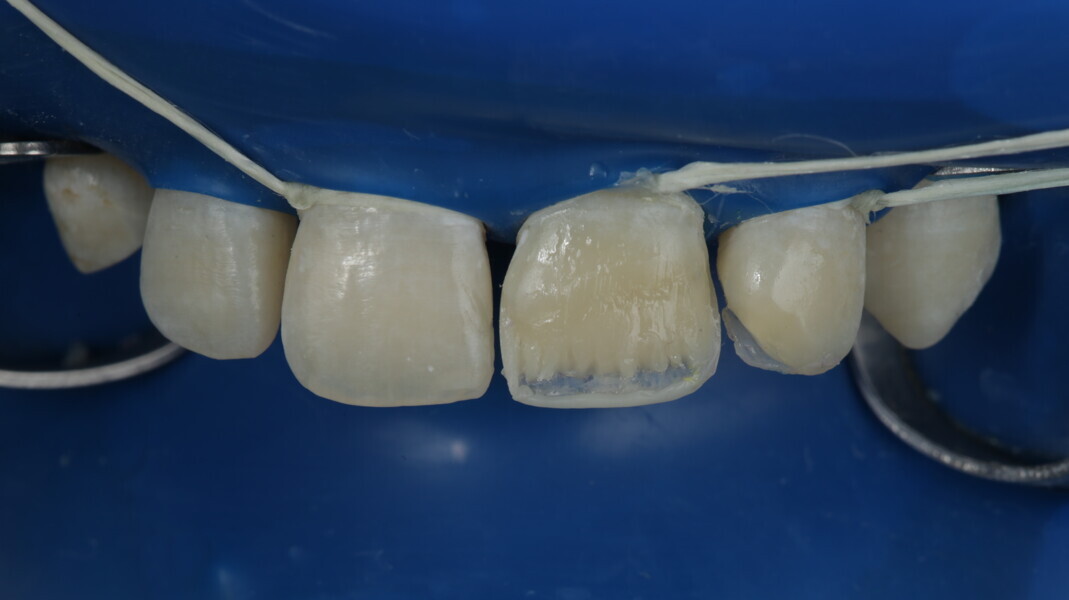

A 10-year-old male patient reported with a complaint of trauma to the upper left central and lateral incisors, involving the enamel and dentin. Direct composite was used in multi-layers and the smile was restored. This article explains detailed steps in the polychromatic layering technique with special emphasis on the finishing and polishing protocol. 3M Espe Filtex Z350 Xt was used with a universal bonding agent.

Fig 25-30: Layering protocol step by step

The article demonstrates how using the right protocols and armamentarium for composite materials can give life-like results in a short time in a minimally invasive way. No single layering technique can ensure a 100% success rate. Regardless of the technique, establishing good secondary and tertiary anatomy and thorough polishing are the key steps that make a restoration look more natural. Composite is the perfect material for allowing correction of mistakes or improvement.